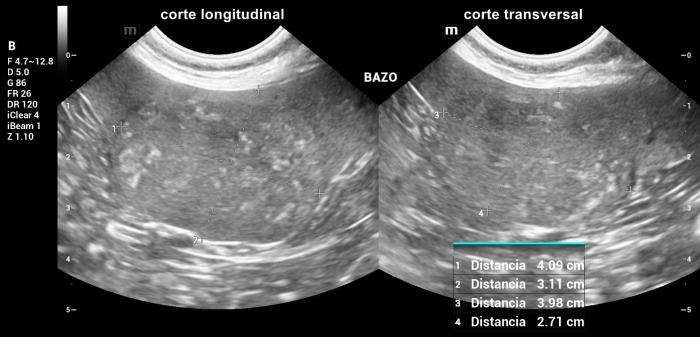

Hallazgos ultrasonográficos (modo B y doppler color): en la cola esplénica se observó una masa ovoide, bien delimitada, de 4.09 × 3.98 × 3.11 cm, con ecogenicidad similar al resto del parénquima esplénico, con focos hiperecoicos transónicos (no mineralizados) dispersos en su interior (Figura 13).

La masa deformaba la arquitectura de la cola esplénica y mostraba vascularización Doppler color positiva, observándose un vaso de gran calibre atravesando toda la masa, sin alteraciones evidenciables (Figura14). No se identificaron otras lesiones esplénicas focales ni alteraciones compatibles con metástasis.

Hallazgos ultrasonográficos (modo B y doppler color): El bazo se encontraba marcadamente agrandado en todos sus ejes, alcanzando la región mesogástrica derecha, con un espesor a nivel del cuerpo de 3.13 cm. Su conformación mostraba plegamiento parcial, compatible con cambios por desplazamiento, aumento de volumen o pérdida de soporte abdominal.